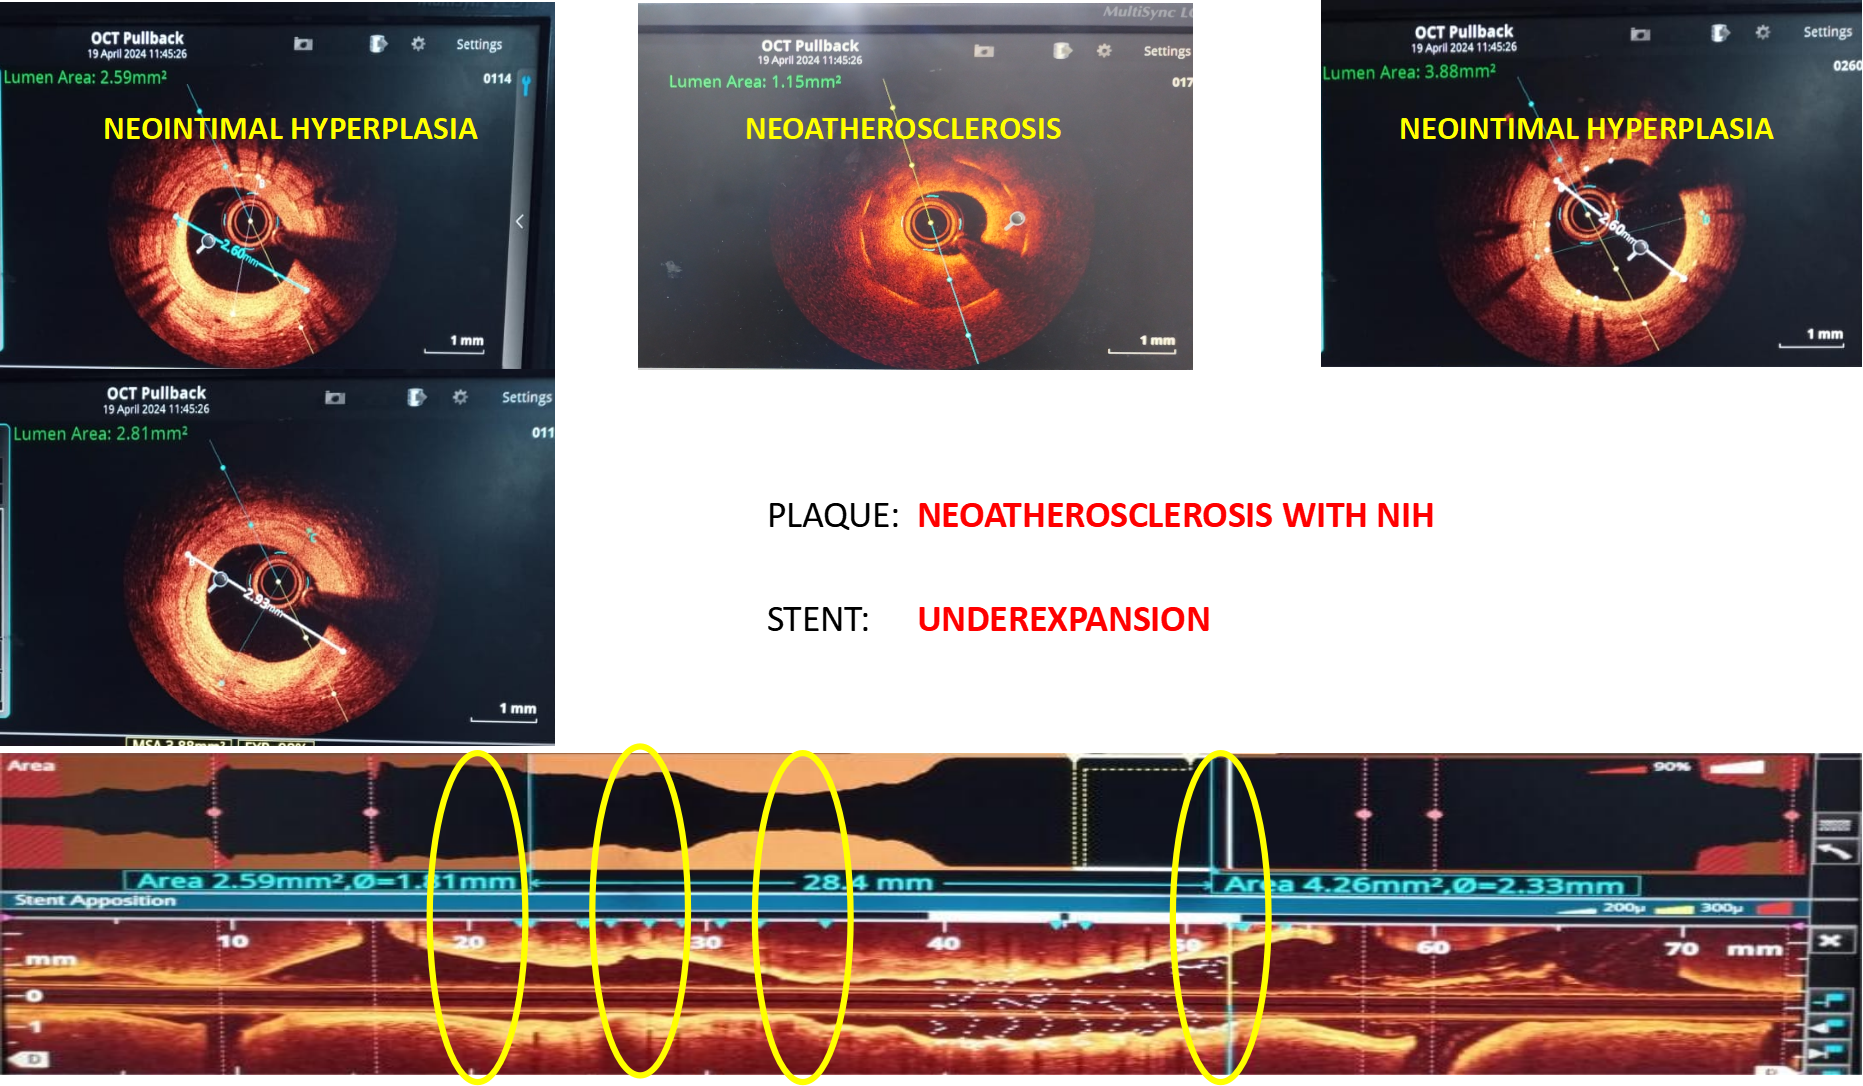

PCI was planned to LAD ISR lesion through right radial approach with 6 French sheath. Optical Coherence Tomography (OCT) was chosen for intracoronary imaging modality as it gives high resolution images to know the plaque morphology, exact mechanism of ISR which help in planning device selection and also to assess the adequacy of lesion preparation. 3.5 EBU 6 French Guiding catheter was taken with Runthrough (Terumo ,Japan) guidewire. Initial OCT ( Dragonfly OpStar catheter, Abbott,USA) run was done. Thick neointimal hyperplasia was seen with neoatheroma in mid portion of ISR lesion. mm as mean diameter in the distal reference segment was 2.9 mm (EEL to EEL) and the measured stent diameter was 2.6 mm. The MLA at the tightest point was 1.15 mm2 . Lesion length was 28 mm. We planned to do plaque modification with cutting balloon and correction of stent under expansion with non compliant balloon followed by drug coated balloon application.Initial plaque modification was done with wolverine (Boston Scientific,USA) 2.5 X 10 mm cutting balloon up to 12 atm from distal to proximal followed by 3.0 x12 mm NC Quantum Apex (Boston Scientific,USA) balloon inflation from 16 to 20 atm. Final OCT run was done which showed intimal micro tears with good lumen gain. 3x 30 mm Agent (Boston Scientific,USA) Drug-Coated Balloon was inflated within the lesion area at 6 atm nominal pressure for 90 seconds. TIMI 3 flow was seen with good vessel expansion on angiography.

Case Summary